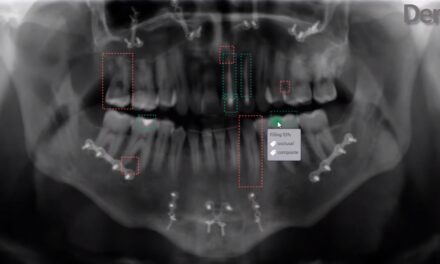

凹痕。AI Auto-Chart牙科auto-charting intraoral和extraoral图像软件自动识别功能。